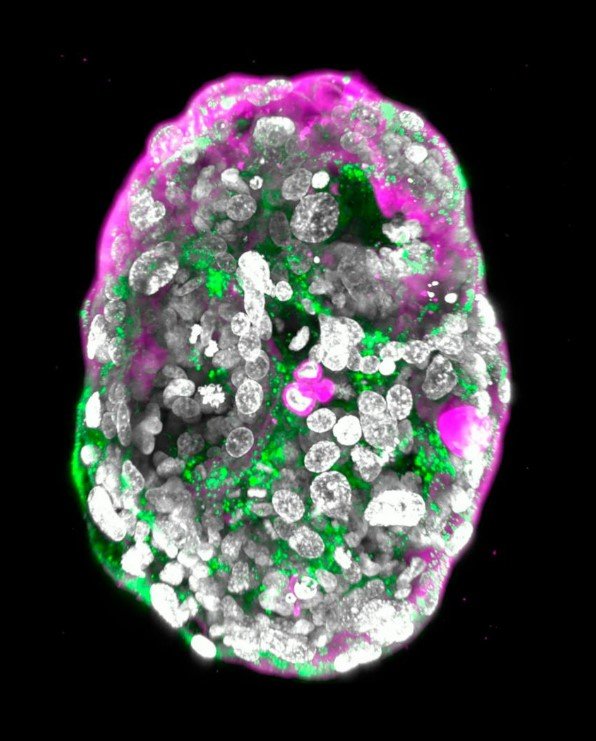

Un equipo de investigación en el Instituto Weizmann de Ciencias, Israel, ha logrado un avance científico crucial al crear modelos completos de embriones humanos sinteticos utilizando células madre de laboratorio. Estos embriones sintéticos, desarrollados sin la necesidad de óvulos ni esperma, fueron cultivados fuera del útero materno hasta el día 14 de desarrollo.

Los embriones sintéticos creados en este estudio exhibieron todas las características típicas de esta etapa, incluyendo componentes como la placenta, el saco vitelino, el saco coriónico y otros tejidos externos esenciales para garantizar un crecimiento adecuado.

El líder del equipo de investigación, Jacob Hanna, destacó que su modelo de embrión humano derivado de células madre proporciona una forma ética y accesible de examinar este período crítico. Imitando con precisión el desarrollo de un embrión humano real, incluyendo la aparición de su arquitectura delicadamente elaborada.